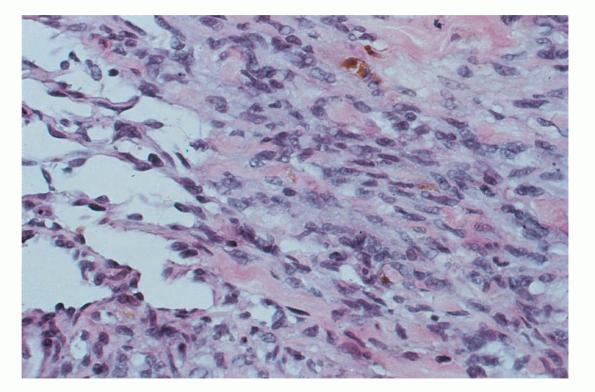

HISTOPATHOLOGY

The histopathology of KS is dependent on the stage of KS development. Early patch-like lesions exhibit rather discrete histopathologic changes, consisting mainly of an increase in the number of dermal vessels, outlined by slightly irregular endothelial cells (Fig. 128-5). These vessels, located mainly in the superficial dermis are parallel to the skin surface, are frequently slightly irregular, and may form bizarre slits and clefts. In the surrounding skin focal hemosiderin, deposits and extravasated erythrocytes can be found as well as a moderate inflammatory infiltrate. Important differential diagnoses of this stage include lymphangioma and granulation tissue.

The pathology of KS plaques is more characteristic and reveals extensive vascular proliferation at all levels of the dermis with multiple dilated and angulated vascular spaces dissecting the collagen leaving a spongy network of collagen tissue. A characteristic sign of KS papules is the presence of solid cords and fascicles of spindle cells arranged between the jagged vascular channels. This biphasic angiomatous and solid tumor morphology changes to a clear-cut sarcomatous morphology with progression of the disease.

Nodular lesions consist predominantly of spindle cells arranged in bundles and interlacing fascicles and interspersed, irregular, slit-like vascular spaces without endothelial linings. Advanced lesions may display pronounced pleomorphism, nuclear atypia, and mitotic figures. At the periphery of solid tumors, (lymph) angiomatous-like portions of KS with bizarre vascular lumina and intravascular and extravasated erythrocytes, as well as siderophages, may be preserved. Erythrocytes, which appear as eosinophilic globules, are trapped within the slits and clefts formed by the spindle cells and erythrophagocytosis are occasionally observed. As in all other stages of KS, a moderate inflammatory infiltrate consisting of lymphocytes, histiocytes, plasma cells, and, sporadically, neutrophils is regularly present.